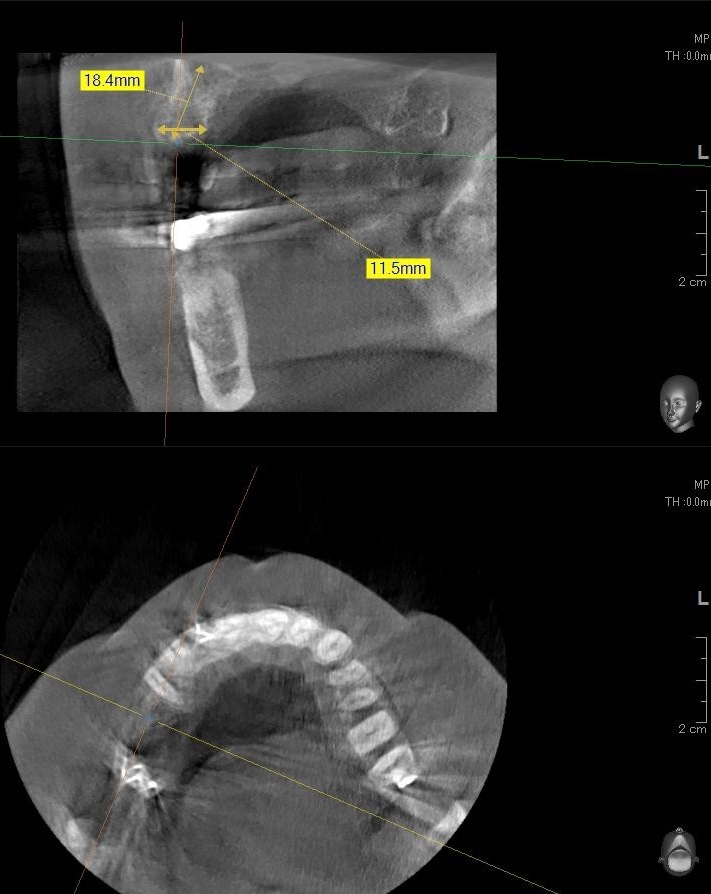

今回の患者様はインプラント植立を希望され、右上5番目・6番目の合計2本の植立が決まりました。

ドリルの先端を細い物から徐々に大きい物に変えながら、植立するインプラント体のネジの部分を除いた胴の部分の太さに合わせた大きさの穴を開けていきます。

開けた穴に、専用道具を使ってネジを締めるように長さ2センチ程のインプラントを骨に埋め込んでいきます。